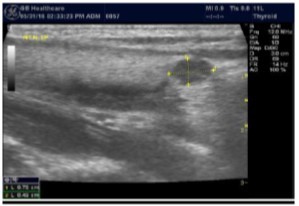

The superficial location of the thyroid gland renders it ideal for ultrasound examination 8. High resolution grey scale images can easily be obtained using high frequency transducer. In the transverse view, normal thyroid gland has the butter fly appearance, with left and right lobes connected with a narrow isthmus, Figure 1A. Both lobes can be imaged separately in the longitudinal plan, Figure 1B

Figure 1A.Normal thyroid gland transverse view